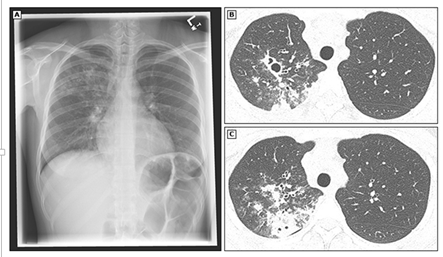

![]() |

Đông đặc thùy trên phổi phải và hang trong lao phổi [9]

- (A) Hình X-quang cho thấy vùng đông đặc và một hang nhỏ ở thùy trên phổi phải.

- (B và C) Hình ảnh cắt lớp vi tính (CT) cho thấy hai hang cạnh nhau, các đám mờ không rõ ranh giới, và vùng đông đặc có hang ở thùy trên phổi phải.